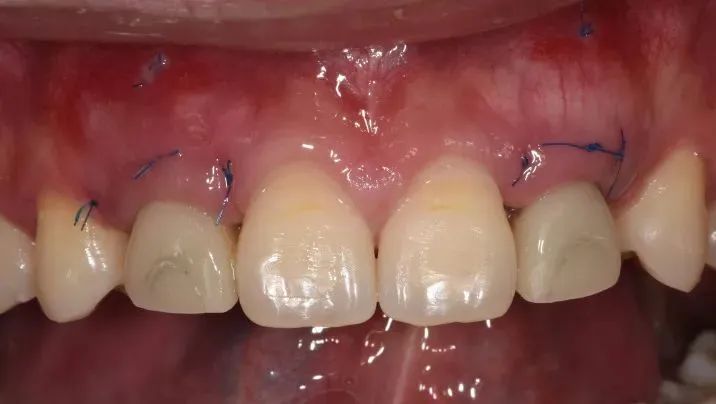

戴入临时修复体正面观

颌面观显示12、22区轮廓丰满度良好

临时修复体邻接良好

12、22牙正中及前伸运动无咬合接触

术后10天拆线,龈乳头处软组织较术后有所改善

术后10天拆线,唇侧褥式缝合保留未拆,拆线后取模制作保持器